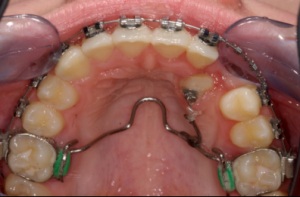

Apparatur zur Beseitigung verlagerter Eckzähne

(Transpalatinalbogen mit Peitsche)